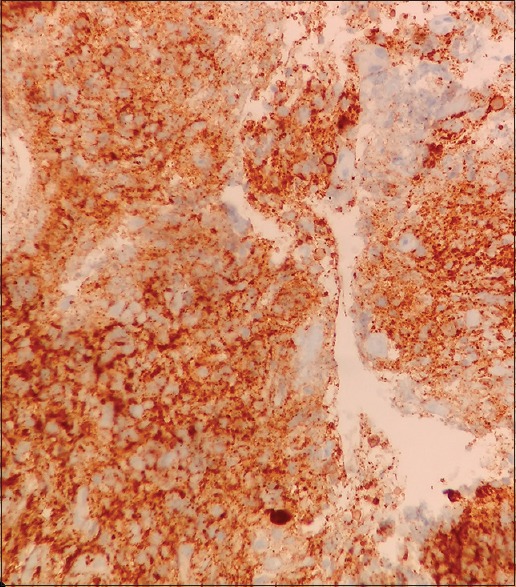

A 65-year-old female with no history of comorbidities was admitted to our hospital on July 5, 2014 with painless lump in her right breast. On detailed history taking, patient had no history of fever, night sweats, or weight loss (B symptoms). Physical examination revealed a hard, nontender, mobile mass of approximately 6 cm × 7 cm occupying all quadrants of the right breast. The contralateral breast was normal. On physical examination, patient had no evidence of cervical, axillary or inguinal lymphadenopathy. Liver and spleen were not palpable. The laboratory tests revealed the following: Hemoglobin of 11.9 g/dl, total leukocyte counts of 10,400/mm3, platelet counts of 48,600/mm3, serum creatinine of 0.72 mg/dl, alkaline phosphatase of 55 IU/L, serum glutamic pyruvic transaminase of 22 IU/L, serum glutamic oxaloacetic transaminase of 13 IU/L, total bilirubin levels of 0.88 mg/dl, serum albumin of 4.34 g/dl, lactate dehydrogenase (LDH) of 172 U/L, and serum uric acid of 4.52 mg/dl. Excisional biopsy performed showed atypical lymphocytic infiltration suspicious of non-Hodgkin's lymphoma (NHL) [Figure 1]. Immunohistochemistry revealed positivity to CD20 [Figure 2], CD79a and MUM1 and negativity to CD2, CD3, CD5, CD10, and AE1. MIB-1 index was 95%. On the basis of histopathologic features, tumor was classified as DLBCL, non-germinal centre B-cell-like (non-GCB DLBCL). Bone marrow aspiration and biopsy were performed and revealed a hypercellular bone marrow with no evidence of lymphomatous infiltration. The cerebrospinal fluid cytological examination was negative for any malignant cells. Computed tomography (CT) of the neck, thorax, abdomen, and pelvis revealed 66 mm × 68 mm × 84 mm large multi-lobulated soft tissue density lesion involving all quadrants of right breast reaching up to the skin [Figure 3]. No systemic lymphadenopathy was detected. The CT findings indicated stage I E of the lymphoma tumor according to the Ann Arbor staging system. The patient received six courses of cyclophosphamide, doxorubicin, vincristine, prednisolone plus rituximab (R-CHOP) chemotherapy. After four courses of R-CHOP, the follow-up chest CT scan showed decreased the size of the right breast mass (6.6 cm × 6.8 cm → 3.4 cm × 1.4 cm) [Figure 4]. After six courses of R-CHOP, the follow-up chest CT scan showed no visible mass in the breast. The patient was put under close observation. At present, after follow-up period of 20 months, the patient is surviving with no evidence of disease and with no morbidities associated with chemotherapy.

| Figure 1:H and E (×40) section showing diffuse proliferation of large cells with high mitotic rate